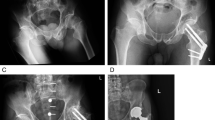

This was a cohort study between January 2014 to June 2018. At our tertiary unit, Prince of Wales Hospital, The Chinese University of Hong Kong, data of all our operation records are recorded into the Clinical Management System database prospectively. This study was approved by The Joint Chinese University of Hong Kong—New Territories East Cluster Clinical Research Ethics Committee (CREC Ref. No. 2019.186). The study protocol is in compliance to Declaration of Helsinki and ICH-GCP. Informed consent was obtained from all subjects and/or their legal guardian(s). Similar to international guidelines, our standard practise is to perform surgery for neck of femur hip fractures patients within 48 h of admission unless medically unfit8,19. Internal fixation is used for “younger patients” and undisplaced fractures in older patients 65 years or older8,19. An ortho-geriatrician specialist identifies and treats correctable comorbidities and optimizes the medical condition for all our hip fracture patients. The inclusion criteria in this study were (1) patients 50 years or older, (2) suffered from a neck of femur fracture, (3) low-energy trauma, (4) internal fixation with cannulated hip screws. Exclusion criteria were (1) patients aged < 50 years old, (2) less than 1 year follow-up, (3) previous fracture on same femur, (4) open fracture, (5) pathological fracture. All recruited patients were subject to internal fixation with 3 cannulated hip screws in an inverted triangle fashion under fluoroscopy with an acceptable Garden alignment index20. Closed reduction was performed for all our patients. Follow-up for patients were 1 year. Information including patient demographics, functional status, fracture type (Garden Classification Type I/II, and Type III/IV)21, Age-adjusted Charlson Comorbidity Index (ACCI) and clinical outcomes were collected for analysis. The “younger” group was defined as age 50–65, and the “elder” group was defined as age above 65. The primary outcome of this study was to determine whether ACCI is associated with increased fracture-related complication rate of neck of femur fractures treated by internal fixation. A complication was defined as fracture non-union, avascular necrosis, screw cut-out, infection and periprosthetic fracture. The secondary outcomes were revision rate, mortality rate, and function after surgery.

Surgical outcomes showed that the complication rate of hip screw fixation for all patients was 21.5% (50 patients), with 24 from the “elderly” hip fracture group and 26 from the “younger” hip fracture group (Table 2). For the “elderly” group, the complication rate was 16.1% with 1 non-union, 5 cut-out and 18 avascular necrosis cases. For the “younger” hip fractures, complication amounted to 31.0% with 5 non-union, 1 cut-out, and 20 avascular necrosis. There were significantly more complications in the “younger” group (p = 0.008). Analysis showed that the younger group had significantly higher non-union (p = 0.01) and avascular necrosis (p = 0.02) compared to the elder group.

Complication rates for all patients with 20 Garden Type I, 10 Garden Type II, 8 Garden Type III and 12 Garden Type IV were 14.5%, 17.5%, 40% and 66.7%, respectively. For elderly patients the complication rates for Garden I and II were 14.2% and 20.9%, respectively. There were no Garden III and IV for elderly patients as these would have undergone arthroplasty. For “younger” patients the failure rates for Garden I, II, III, and IV were 15.6%, 7.1%, 40% and 66.7%, respectively. The complications rate of the undisplaced group (Garden Type I and II) was significantly lower than the displaced group (Garden Type III and IV) (p < 0.01).

After surgery for internal fixation, 95 patients (40.8%) walked unaided, 65 (27.9%) with a stick, 29 (12.4%) with a frame, and 32 (13.7%) were non-ambulatory. 126 patients (54.1%) required a walking aid, 46 needed assistance (19.7%), 65 (24.5%) were non-ambulant and only 95 were independent walkers. For the “younger” group, 73.8% of the patients retained function at least comparable to their premorbid. As for the “elder” group, only 51.0% retained function at least comparable to their premorbid. The summary of patient mobility pre-operative and post-operative outcomes are shown in Tables 4 and 5. Of the 50 patients that suffered from complications, 25 patients had a revision surgery within the 6 months of follow-up, with 15 in the “younger” group and 10 in the elderly group. Of the 15 “younger” patients, 7 underwent revision to total hip replacement, 7 underwent revision to bipolar hemiarthroplasty, and 1 underwent removal of hip screws. In terms of mobility after revision surgery, 6 walked unaided, 8 walked with a stick, and 1 was wheelchair bound. For the elderly group, 5 underwent revision to total hip replacement, 3 underwent hemiarthroplasty, 1 underwent removal of hip screws, and 1 underwent excisional arthroplasty. In terms of mobility after revision surgery, 1 walked unaided, 2 walked with a stick and 2 were wheelchair bound. The summary of revision surgery is shown in Table 2.